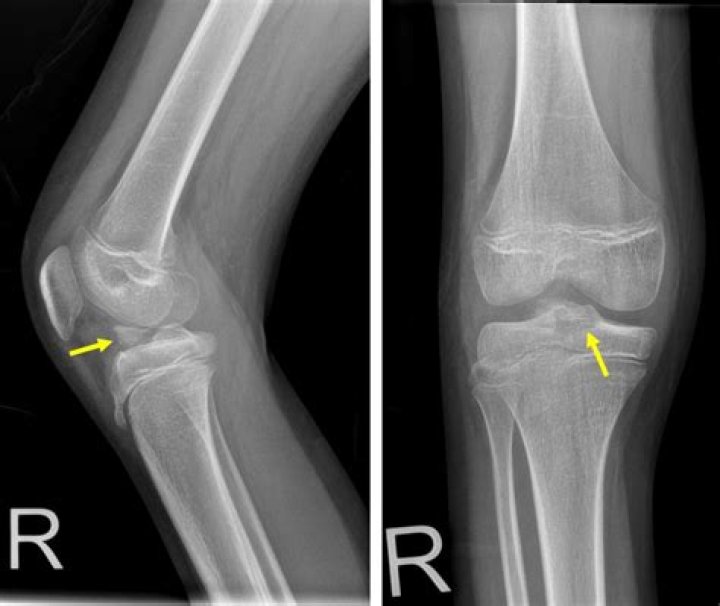

The knee joint remains particularly susceptible to avulsion fractures due to its numerous tendinous, ligamentous, and meniscal attachments. An avulsion fracture involves the detachment of a bone fragment that results from the pulling away of a ligament, tendon, or joint capsule from its point of attachment on a bone.

An avulsion fracture is an injury to the bone in a location where a tendon or ligament attaches to the bone. When an avulsion fracture occurs, the tendon or ligament pulls off a piece of the bone. Avulsion fractures can occur anywhere in the body, but they are more common in a few specific locations.